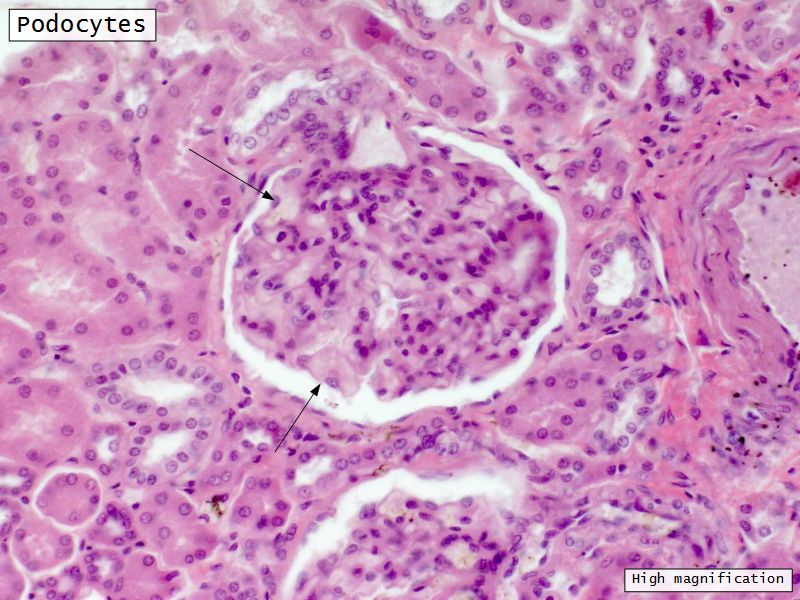

Epithelium layers

- Capillary endothelium

- Visceral layer of epithelium

- Podocytes

- Resting on glomerular basement membrane

- Capsular space

- Parietal layer of epithelium

- Simple squamous epithelium

Podocytes

- Visceral layer of epithelium

- Protrude into capsular space

- Attached to basement membrane

- Long cytoplasmic extensions

- Primary processes

- Secondary processes

- Podocyte feet

- Tightly spaced

- Filtration slits 20 - 30 nm wide